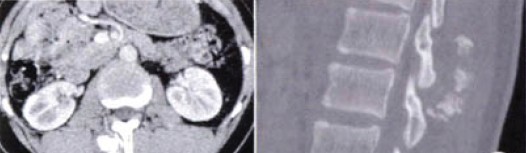

,16岁。腰背部疼痛1周入院。患者于1周前无明显诱因出现腰部隐痛、钝痛,持续性、渐加重。无发热.咳嗽咳痰。无腹痛腹泻。无肢体麻木及大小便障碍。既往体健,家族史无特殊。人院查体:生命体征正常。专科检查:脊柱呈生理性弯曲,T12~L2棘突及右旁明显压痛、叩痛,T12~L2棘突右旁扪及一鸡蛋大小包块,压痛,质硬,固定。余正常。入院平扫及增强CT示:T12~L1段右侧竖脊肌内软骨类肿瘤可能(图1a~1c)。积极准备在复合全麻下行肿瘤切除术。术中见:T12~L2水